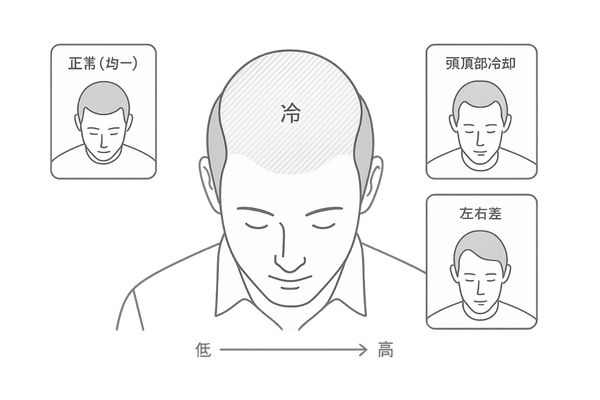

頭皮の血行パターンの比較

| パターン | サーモグラフィー上の特徴 | 示唆される状態 |

|---|---|---|

| 正常型 | 頭部全体が均一な暖色系 | 血行が良好で健康的 |

| 頭頂部冷却型 | 頭頂部が周囲より低温 | 男性型脱毛症(AGA)のリスク |

| まだら型 | 温度のムラが全体に見られる | 自律神経の乱れ、ストレス |

「正常な頭皮」の温度分布とは

健康で血行が良好な頭皮は、サーモグラフィーで見ると、中心部から外側に向かってなだらかに温度が分布し、全体的に均一な暖かい色を示します。

特に、血管が太く血流量の多い側頭部は比較的高温になる傾向があります。左右の温度差が少なく、極端な低温部分が見られないことが、正常な状態の一つの目安となります。

「血行不良の頭皮」に見られる特徴

血行不良の頭皮には、いくつかの典型的な特徴が現れます。最も一般的なのは、薄毛が進行しやすい頭頂部や前頭部が、血流の保たれやすい側頭部や後頭部に比べて明らかに低温になるパターンです。

これは、重力や筋肉の影響で頭頂部の血流が滞りやすいことに起因します。

部位による温度差とその意味

頭皮の部位によって血行のしやすさには違いがあり、それが温度差として現れます。側頭部や後頭部は、筋肉の動きが比較的多く血管も太いため、血流が保たれやすく温度が高い傾向にあります。

一方、頭頂部は帽状腱膜という硬い膜で覆われており、筋肉が少なく血管も細いため、血流が滞りやすく温度が低くなりがちです。

この部位ごとの温度差が極端に大きい場合、それは血行不良が進行しているサインであり、特に男性型脱毛症(AGA)のリスク評価において重要な指標となります。